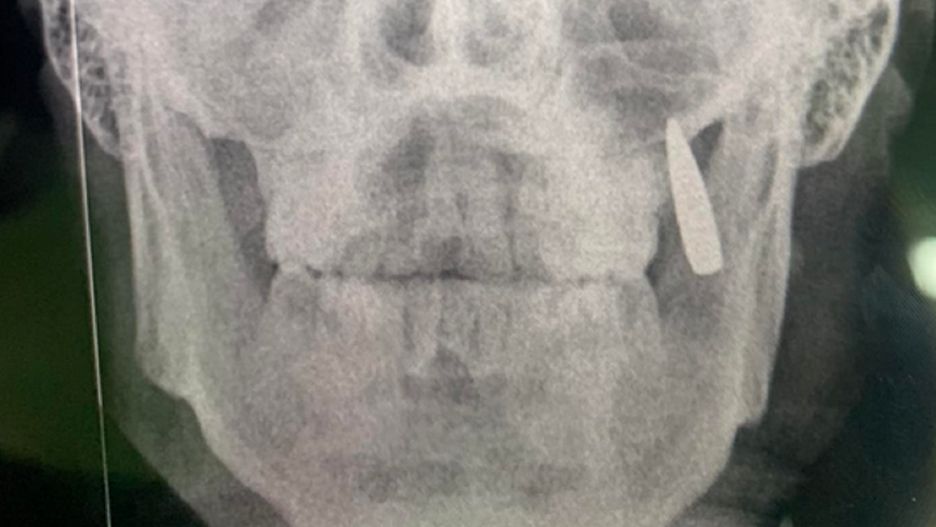

Nabój utkwił w szczęce żołnierza.Nabój utkwił w szczęce żołnierza.

Po zrobieniu zdjęcia rentgenowskiego okazało się, że w twarzy żołnierza znajduje się... pocisk. To właśnie nabój wybił dwa zęby mężczyzny i utkwił w ich miejscu. Na szczęście obrażenia spowodowane tym nabojem nie były groźne.

Robię rentgen, zamiast dwóch zębów kula utknęła w szczęce. No, to jest implant... - dodała Oksana.